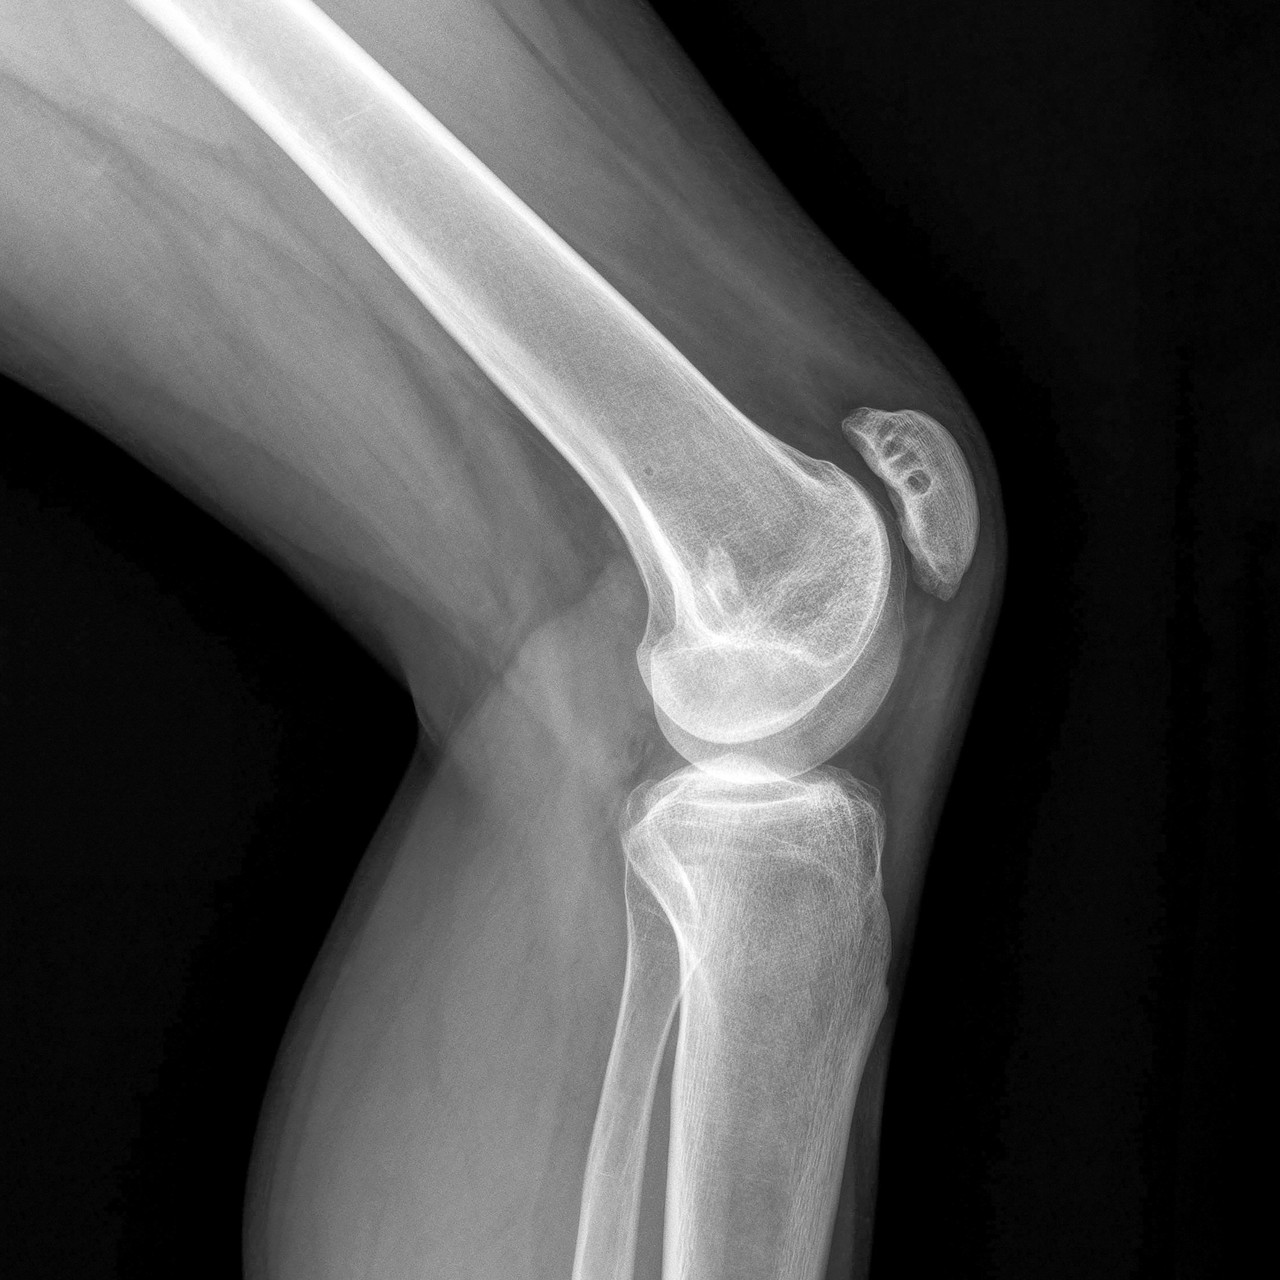

영상의학 검사

퇴행성 관절염은 영상을 정확히 판독할 수 있는 정형외과 전문의의 역할이 중요합니다. 엑스레이와 환자의 증상만으로도 90% 이상 진단할 수 있습니다.

퇴행성 관절염은 운동 후 또는 관절을 많이 사용한 후에 통증이 심해지는 것이 일반적이고 쉬면 통증이 줄어드는 경우가 많습니다. 엑스레이에서도 두 질환을 구별할 수 있는데 퇴행성관절염의 경우에는 관절의 간격감소와 골극의 형성이 비교적 고르게 나타나는 반면, 류마티스 관절염의 경우에는 중간마디나 발목 등의 큰 관절에도 나타나며 관절의 파괴, 골 용해가 나타나는 경우가 많습니다.

일반적으로 피검사를 하지 않아도 엑스레이와 환자의 증상만 자세히 살피면 류마티스 관절염과 퇴행성 관절염을 구별할 수 있습니다.